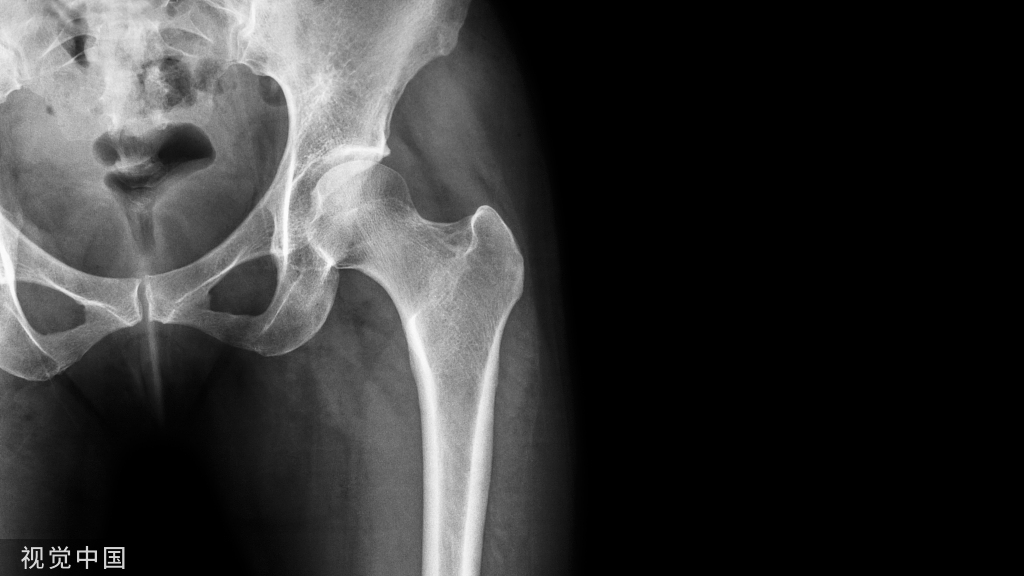

痛风属于代谢性疾病范畴,是由于尿酸盐结晶沉积于关节、软组织和肾脏,引起关节炎、皮肤病变及肾脏损害等。有调查发现约1/3的HUA患者会发展为痛风。

- ②急性痛风性关节炎;

- ④慢性痛风石及慢性痛风性关节炎。